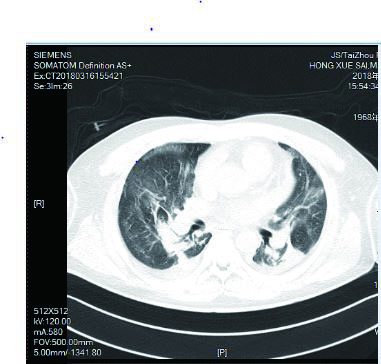

1.2 临床表现和检查患者初期有咳嗽症状,但未在意,患者回家24 h后咳嗽症状加重,伴胸闷气喘,全身大汗淋漓,家属立即将其送至本院急诊,为进一步诊治拟“有机氟中毒”收住入院。入院时体检:神志清楚,T:36.5℃,R: 57次/min,BP: 146/71 mmHg,胸廓对称无畸形,呼吸急促,听诊双肺呼吸音清晰,可闻及大量湿性啰音,心率112次/min,心律齐,心音正常,各瓣膜听诊区未闻及病理性杂音及心包摩擦音,四肢关节正常,双下肢无水肿,深浅生理反射正常,病理反射阴性,脑膜刺激征阴性。辅助检查:白细胞计数10.45×109/L,中性粒细胞91.9%;C-反应蛋白14.81 mg/L, 无创机械通气支持下血气分析pH7.28,PCO2 50 mmHg, PO2 57 mmHg, Lac 3.0 mmol/L(FiO2 50%),为Ⅱ型呼吸衰竭,给予无创呼吸机辅助呼吸、激素冲击、解痉平喘等抢救治疗。急诊胸部CT检查提示:两肺散在斑片状模糊影,密度不均,边界不清(图 1),进ICU床边胸片提示:两肺散在斑片状模糊影(图 2)。根据GBZ5—2016《职业性氟及其无机化合物中毒的诊断》的诊断标准,该患者诊断为职业性急性重度有机氟中毒。

| 图 1 3月10日胸部CT |